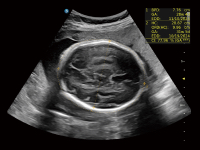

作為開(kāi)立醫(yī)療全新打造的超高端旗艦超聲產(chǎn)品,從探頭抬起喚醒開(kāi)啟掃查到多維探頭發(fā)射接收,通過(guò)先進(jìn)的場(chǎng)成像發(fā)射、自適應(yīng)聚合重建等技術(shù),基于RF Data原始射頻數(shù)據(jù)在圖像生成、高端功能等方面實(shí)現(xiàn)突破,為婦產(chǎn)科、兒科提供全方位臨床解決方案。

夢(mèng)溪?P80以“關(guān)愛(ài)女性”為基石,提供全方位的解決方案,量身定制以滿足女性的健康需求,涵蓋婦科、生殖健康檢查、產(chǎn)前篩查及產(chǎn)后康復(fù)等領(lǐng)域。